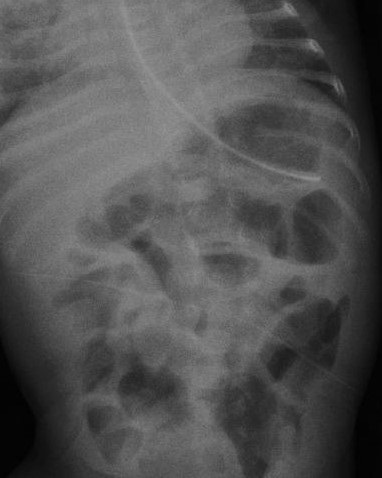

The baby responded to conservative management with antibiotics and withholding of feeds. Serial x-rays of the abdomen showed gradual resolution of the gastric pneumatosis (Fig. 2). Small formula feeds were reintroduced through the orogastric tube after 5 days and gradually graded up to full feed by Day 138 of life. The baby briefly required oxygen via nasal cannula at the time of developing gastric pneumatosis, which was weaned and stopped by day 133 of life and since then saturations were maintained in room air with stable hemodynamic status.

Figure 2

Follow-up X-ray of the abdomen showing resolution of gastric pneumatosis.